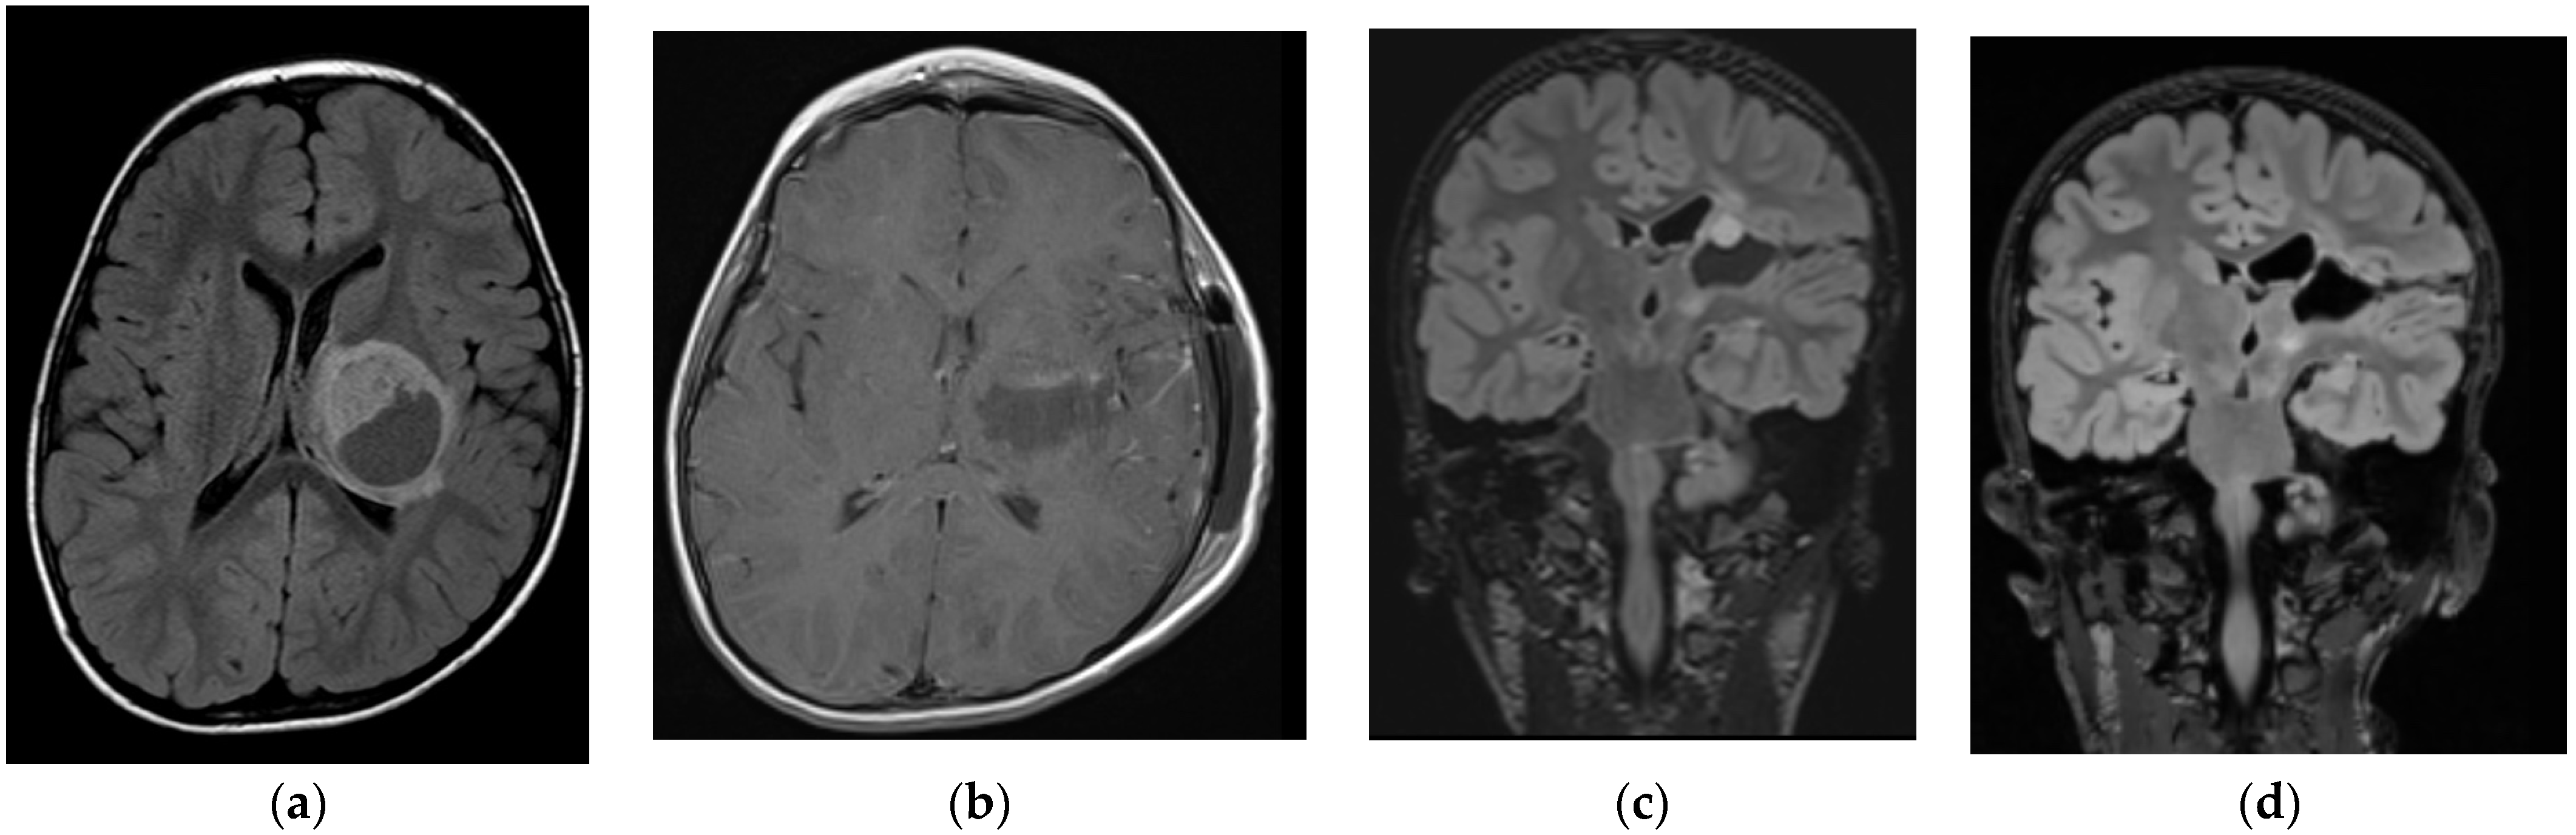

| Case # | Age y/o | Histology | Grade of Resection | Adjuvant Treatment | Complications | Follow Up in Months | Recurrence | Clinical Status |

|---|---|---|---|---|---|---|---|---|

| Low Grade | ||||||||

| 1 | 9 | Pilocytic astrocytoma | GTR | No | No | 96 | No | ANED |

| 2 | 17 | Pilocytic astrocytoma | GTR | No | No | 84 | No | ANED |

| 3 | 7 | Pilocytic astrocytoma | GTR | No | No | 12 | No | ANED |

| 4 | 15 | DNET | GTR | No | No | 60 | No | ANED |

| 5 | 4.6 | Pilocytic astrocytoma | GTR 2× | No | No | 40 | Yes | ANED |

| 6 | 16 | Pleomorphic xanthoastrocytoma | STR | No | No | 42 | No | ASD |

| 7 | 11 | Pilocytic astrocytoma | GTR | No | No | 18 | No | ANED |

| 8 | 5 | Ganglioglioma | STR | No | No | 16 | No | ASD |

| High Grade | ||||||||

| 9 | 18 | Astrocytoma WHO gr. 4 | GTR | CR * | No | 21 | Yes | DOD |

| 10 | 15 | Mut. diffuse midline glioma | STR | CRI * | Hydrocephalus—VP drainage | 15 | Yes | DOD |

| 11 | 11 | Mut. diffuse midline glioma | GTR | CRI * | Hydrocephalus—VP drainage | 6 | No | ANED |